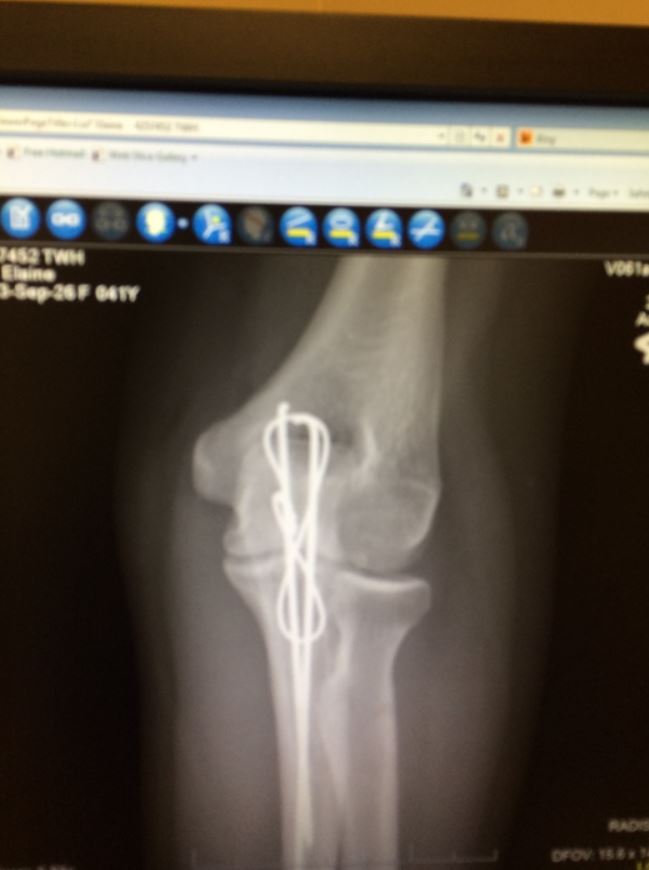

Anyway, at the time they inserted a rod to reattach my elbow which had fractured off and was floating away down my forearm. The rod itself is now, sort of, sliding out. See it on the x-rays? How close it is to my skin?